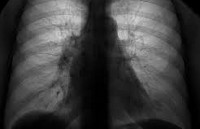

Стандартом диагностики рака легкого служит сочетание рентгенологических и эндоскопических данных, подкрепленных результатами морфологического исследования. На обзорной рентгенограмме легких аденокарцинома выявляется в виде округлой тени, иногда может определяться плевральный выпот. Рентгенологическими признаками бронхиолоальвеолярного рака служат ограниченные участки затемнений с полосовидными зонами повышенной прозрачности или множественные очаговые фокусы.

Более точную информацию о расположении опухоли, заинтересованности лимфоузлов и органов средостения позволяет получить КТ легких. Бронхоскопия с биопсией наиболее информативна при центральном расположении аденокарциномы легкого. Вместе с тем, даже при периферическом росте опухоли в ходе эндоскопического исследования может быть получен секрет бронхов для проведения цитологического исследования. В отдельных случаях общий алгоритм диагностики рака легкого дополняется проведением УЗИ плевральных полостей, торакоцентеза, прескаленной биопсии.